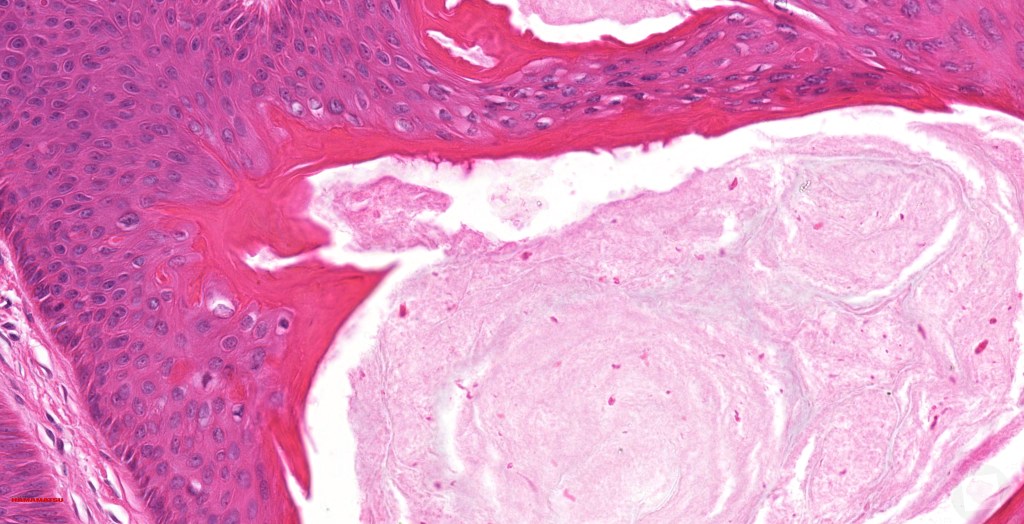

•PAS+ve cytoplasmic vacuolation indicating outer root sheath differentiation

•Infundibular>trichilemmal keratinization